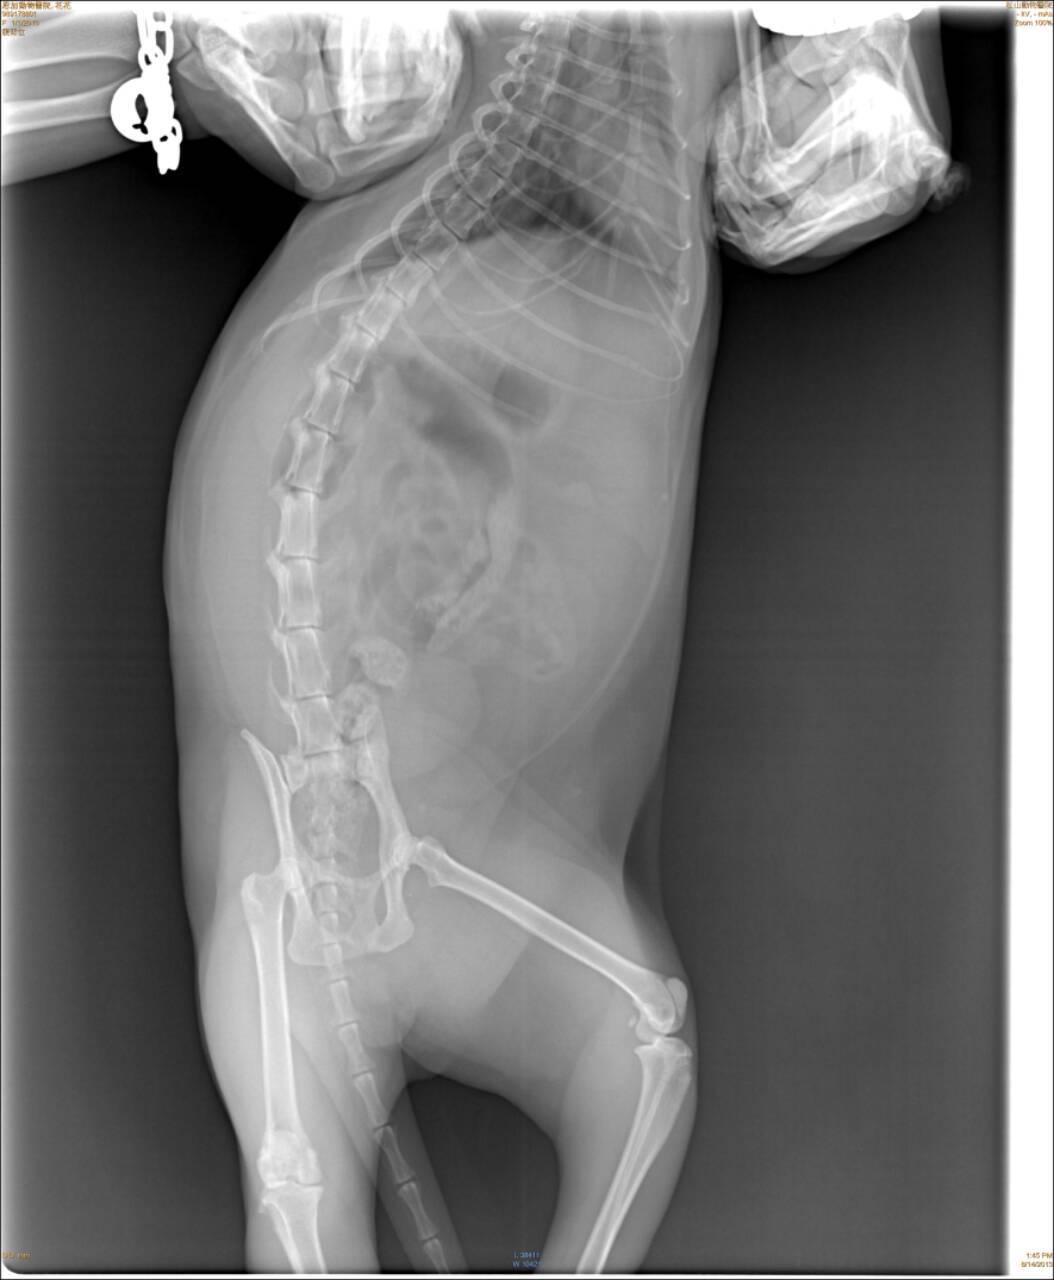

趕緊送往配合醫院~恩加動物醫院檢查。經觸診及照X光片,醫生表示花花的左後肢腳跟關節粉碎性骨折、脫水、白血球上升到三萬多。

經與醫師討論請教,醫師建議不宜動刀、因為粉碎性骨折無法接合只能打板固定,但如此一來反而會讓腳僵直無法動彈。預計先施打點滴補充體力、抗生素、止痛針,等貓咪穩定後要讓貓自行活動進行腳的復健,但已不適合回到接頭流浪了。

8/14住院,照X光片。